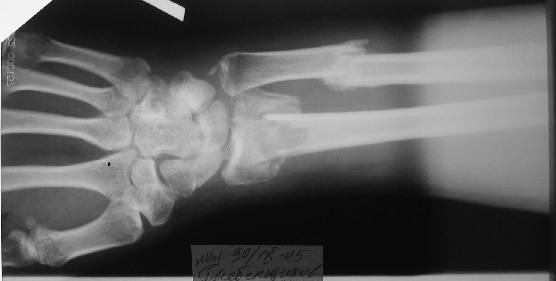

Больному 27 лет. Травма 2 месяца назад, проводилась закрытая репозиция. Контрольные снимки 3 недели назад (смотреть вложение).

Планируем провести открытую репозицию фиксацию пластинами.

Обдумываем, как провести репозицию? Предварительно провести дистракцию аппаратом внешней фиксации за нескольких дней до открытой репозиции или во время открытой репозиции?

Первоначальное впечатление: если край проксимального отломка лучевой кости не давит на срединный нерв и не нарушает скольжение сгибателей, то достаточно быстро пациент сможет вернуться к труду при продолжении консервативного лечения. Укорочение на 15 мм для неопорного (да и для опорного тоже) сегмента некритично. Имеющиеся осевые смещения вполне компенсируются запасом диапазона фукции суставов. Если край проксимального отломка мешает -- можно резецировать его, не разрушая сфорировавшегося к сегодняшнему дню сращения.